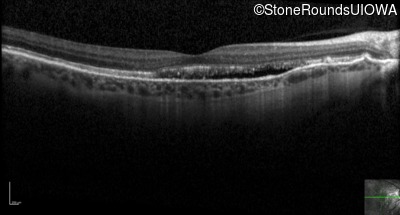

Optical Coherence Tomography - Right - 20/25 +2 sc

Exemplar / OCT Stack

OCT Stack